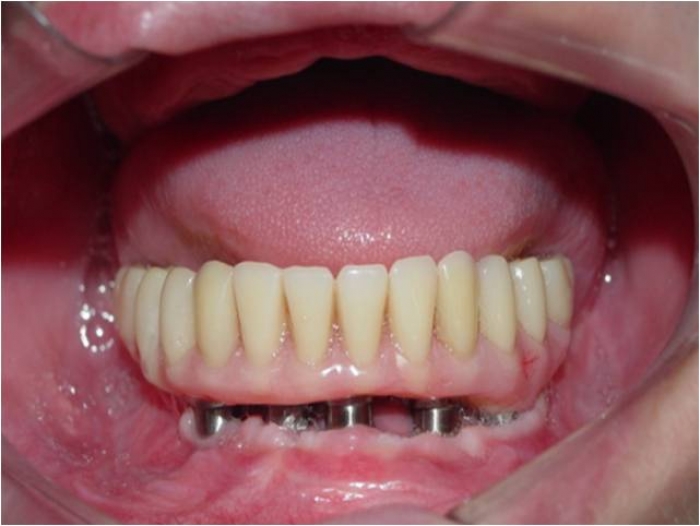

Imagens dos implantes inferiores e prótese fixa provisória imediata

Próteses fixas em resina superior e inferior sobre implantes